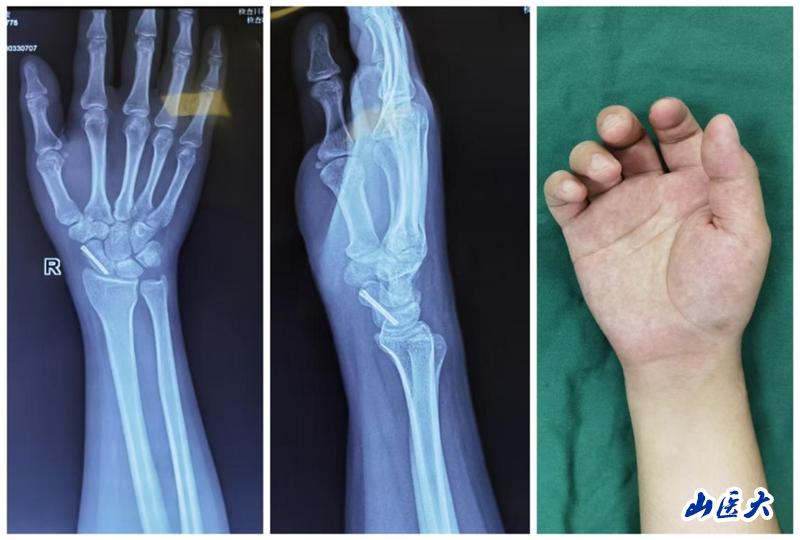

近日,我校第二医院西院区显微手外科王建国主任团队成功为一名舟骨骨折的患者实施微创经皮螺钉内固定手术,全程仅通过一个2mm的小创口就完成手术,可以形象地称为“一针到位”。

患者是一位年仅21岁的男性患者,他在上学途中不慎骑自行车摔倒,导致右腕部剧烈疼痛、肿胀并活动受限。经过X线片检查,确诊为右侧舟骨骨折。患者曾在重庆某三甲医院接受石膏固定术,但为寻求更专业的治疗,选择到我校第二医院西院区就诊。

考虑到患者年轻且希望尽快恢复,王建国团队在详细讨论并与患者及家属充分沟通后,决定采用微创经皮螺钉复位内固定术这一先进治疗方法。手术过程中,医疗团队借助C臂机透视引导进行精准定位,仅通过一个微小的2mm切口,就成功置入螺钉完成了内固定。术后,患者疼痛明显缓解,复查X线片显示螺钉位置良好,腕关节功能活动也恢复得相当不错。